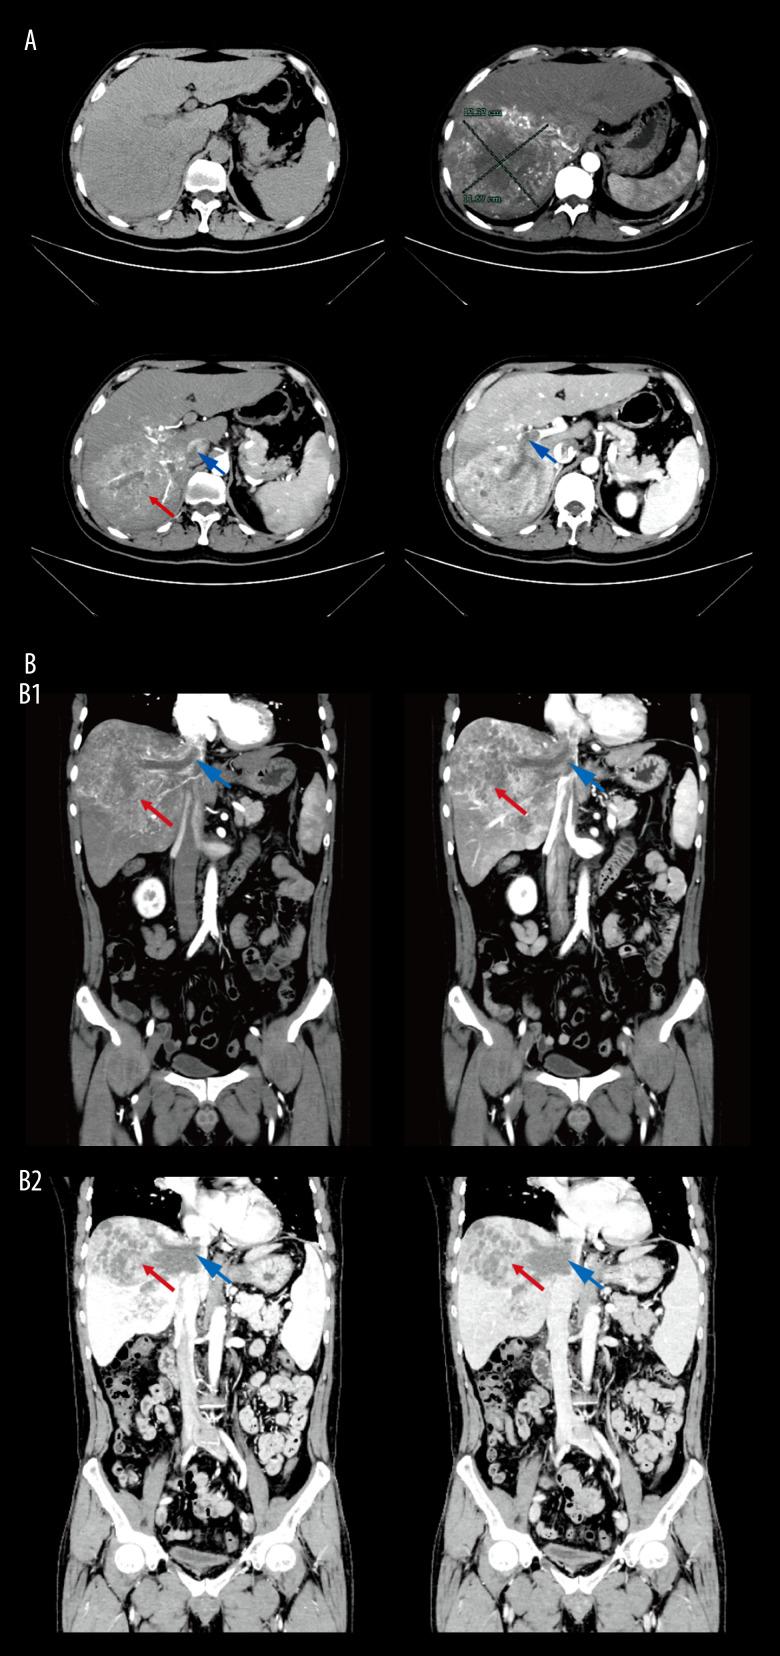

BACKGROUND Hepatocellular carcinoma (HCC) with vascular invasion at advanced stage is not indicated for surgical options. Conversion therapy is used for unresectable HCC to downstage. Chemotherapy can be more precisely targeted to HCC by using hepatic artery infusion. Bevacizumab and sintilimab are available systemic therapies for HCC. This report describes a 50-year-old man with advanced HCC associated with multiple venous tumor thromboses treated with hepatic artery infusion chemotherapy (HAIC) combined with bevacizumab and sintilimab conversion therapy. CASE REPORT A 50-year-old man was admitted to the hospital due to elevated alpha-fetoprotein (AFP) level in July 2022. Abdominal computed tomography angiography (CTA) revealed a large HCC with multiple venous tumor thromboses. Pulmonary CTA detected arterial embolism and multiple solid nodules. He received HAIC combined with bevacizumab and sintilimab every 3 weeks, and achieved partial response after 3 cycles. However, in March 2023, levels of AFP and protein induced by vitamin K absence-II (PIVKA-II) were re-elevated, showing some pulmonary nodules were enlarged, which was confirmed as pulmonary metastases by positron emission tomography/computed tomography (PET/CT). Subsequently, transarterial chemoembolization (TACE) with bevacizumab and sintilimab was performed, and stereotactic body radiation therapy (SBRT) was used to treat pulmonary metastases. Skull metastasis appeared in March 2024, requiring further local radiotherapy. Despite this, the patient has survived for over 26 months, with a progression-free survival (PFS) of 8 months. CONCLUSIONS HAIC combined with bevacizumab and sintilimab can alleviate primary HCC and tumor thromboses, and further local radiotherapy can control the progression of distant metastases, prolonging the survival time of patients with advanced HCC.

一名50岁男性因2022年7月甲胎蛋白(AFP)水平升高入院。腹部计算机断层血管造影(CTA)显示一个大的HCC伴有多个静脉瘤栓。肺部CTA检测到动脉栓塞和多个实性结节。他每3周接受一次HAIC联合贝伐单抗和信迪利单抗治疗,3个周期后达到部分缓解。然而,2023年3月,AFP和维生素K缺乏诱导蛋白-II(PIVKA-II)水平再次升高,显示一些肺结节增大,正电子发射断层扫描/计算机断层扫描(PET/CT)证实为肺转移。随后,进行了联合贝伐单抗和信迪利单抗的经动脉化疗栓塞(TACE),并使用立体定向体部放射治疗(SBRT)治疗肺转移。2024年3月出现颅骨转移,需要进一步局部放疗。尽管如此,患者已存活超过26个月,无进展生存期(PFS)为8个月。